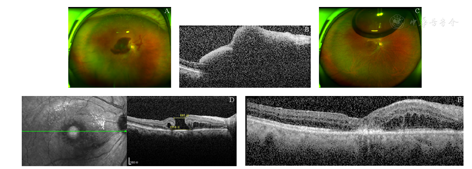

病例1:患者,女,72岁,因"右眼视物不清5 d"就诊。患者主诉无眼红、眼痛等其他症状,否认高血压、糖尿病等其他全身病史。眼科检查:最佳矫正视力(BCVA)为右眼HM/眼前,左眼0.8;双眼眼压14 mmHg(1 mmHg=0.133 kPa)。裂隙灯显微镜检查:双眼晶状体皮质混浊;右眼后极部视网膜下可见约15 PD大暗红色出血灶(见图1A),覆盖黄斑,左眼眼底正常。光学相干断层扫描(OCT)检查示:视网膜组织高度隆起,视网膜下低反射信号,黄斑中心凹厚度1 120 μm(见图1B)。根据以上专科检查及病史,诊断:右眼黄斑下出血;双眼年龄相关性白内障。给予患者右眼玻璃体切割手术,清除内界膜下积血,见视网膜深层仍有6 PD积血,视网膜上血管弓近视盘处动脉血管瘤样扩张,增加诊断右眼视网膜大动脉瘤。术中应用38G针头于视网膜出血灶区穿刺,视网膜下注入组织型纤溶酶原激活剂(Tissue plasminogen activator,t-PA)25 μg(0.025 ml),玻璃体腔填充16% C3F8气体,术中行"白内障超声乳化+人工晶状体植入"术。术后嘱俯卧位。患者于1周后检查发现右眼玻璃体腔气体填充,黄斑区视网膜下积血吸收。患者于术后1个月复查,右眼视力0.05,黄斑中心凹可见约1/2 PD裂孔(见图1C,图1D),给予黄斑裂孔内界膜填塞术,玻璃体腔注入16% C3F8气体,术后俯卧位,1个月后黄斑裂孔愈合(见图1E),右眼BCVA 0.05。

A:右眼黄斑区视网膜下可见约15 PD大小暗红色出血灶;B:OCT示视网膜下大量低反射信号;C:玻璃体切割联合视网膜下注射t-PA术后1个月黄斑下积血全部被吸收,黄斑中心凹见圆形裂孔;D:OCT示术后1个月发现黄斑裂孔形成,直径约885 μm,基底部直径约1 518 μm;E:内界膜填塞术后1个月可见黄斑裂孔愈合

A: There was a dark red subretinal hemorrhage in the macular region of the right eye, about 15 PD in size. B: The OCT showed a lot of subretinal hyporeflexia in the right eye. C: The round macular hole was found after the submacular hemorrhage was absorbed 1 month after vitrectomy combined with subretinal injection of t-PA. D: One month after the operation, OCT showed a macular hole with a diameter of 885 μm and a basal diameter of 1 518 μm in the right eye. E: The macular hole healed 1 month after internal limiting membrane tamponade in the right eye.